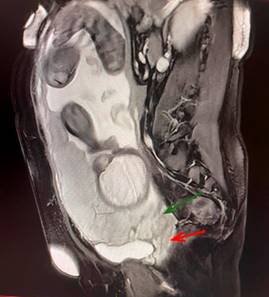

Femenino de 32 años, cuarta gesta, una cesárea, dos abortos, O Rh negativo. Cursó con amenaza de aborto y colestasis intrahepática del embarazo. En la semana 29, el ultrasonido confirmó “placenta previa central total”; la MRI del 25 de agosto del 2022 mostró embarazo de 32 semanas, placenta previa total, datos de acretismo (percreta), extensión al cérvix (Figura 1). Se realizó cesárea histerectomía el 9 de septiembre de 2022, a las 35.3 semanas.

Figura 1: Corte sagital en T12 con presencia de placenta de implantación anterior y previa central total con discontinuidad de la línea hipointensa en el Cérvix.